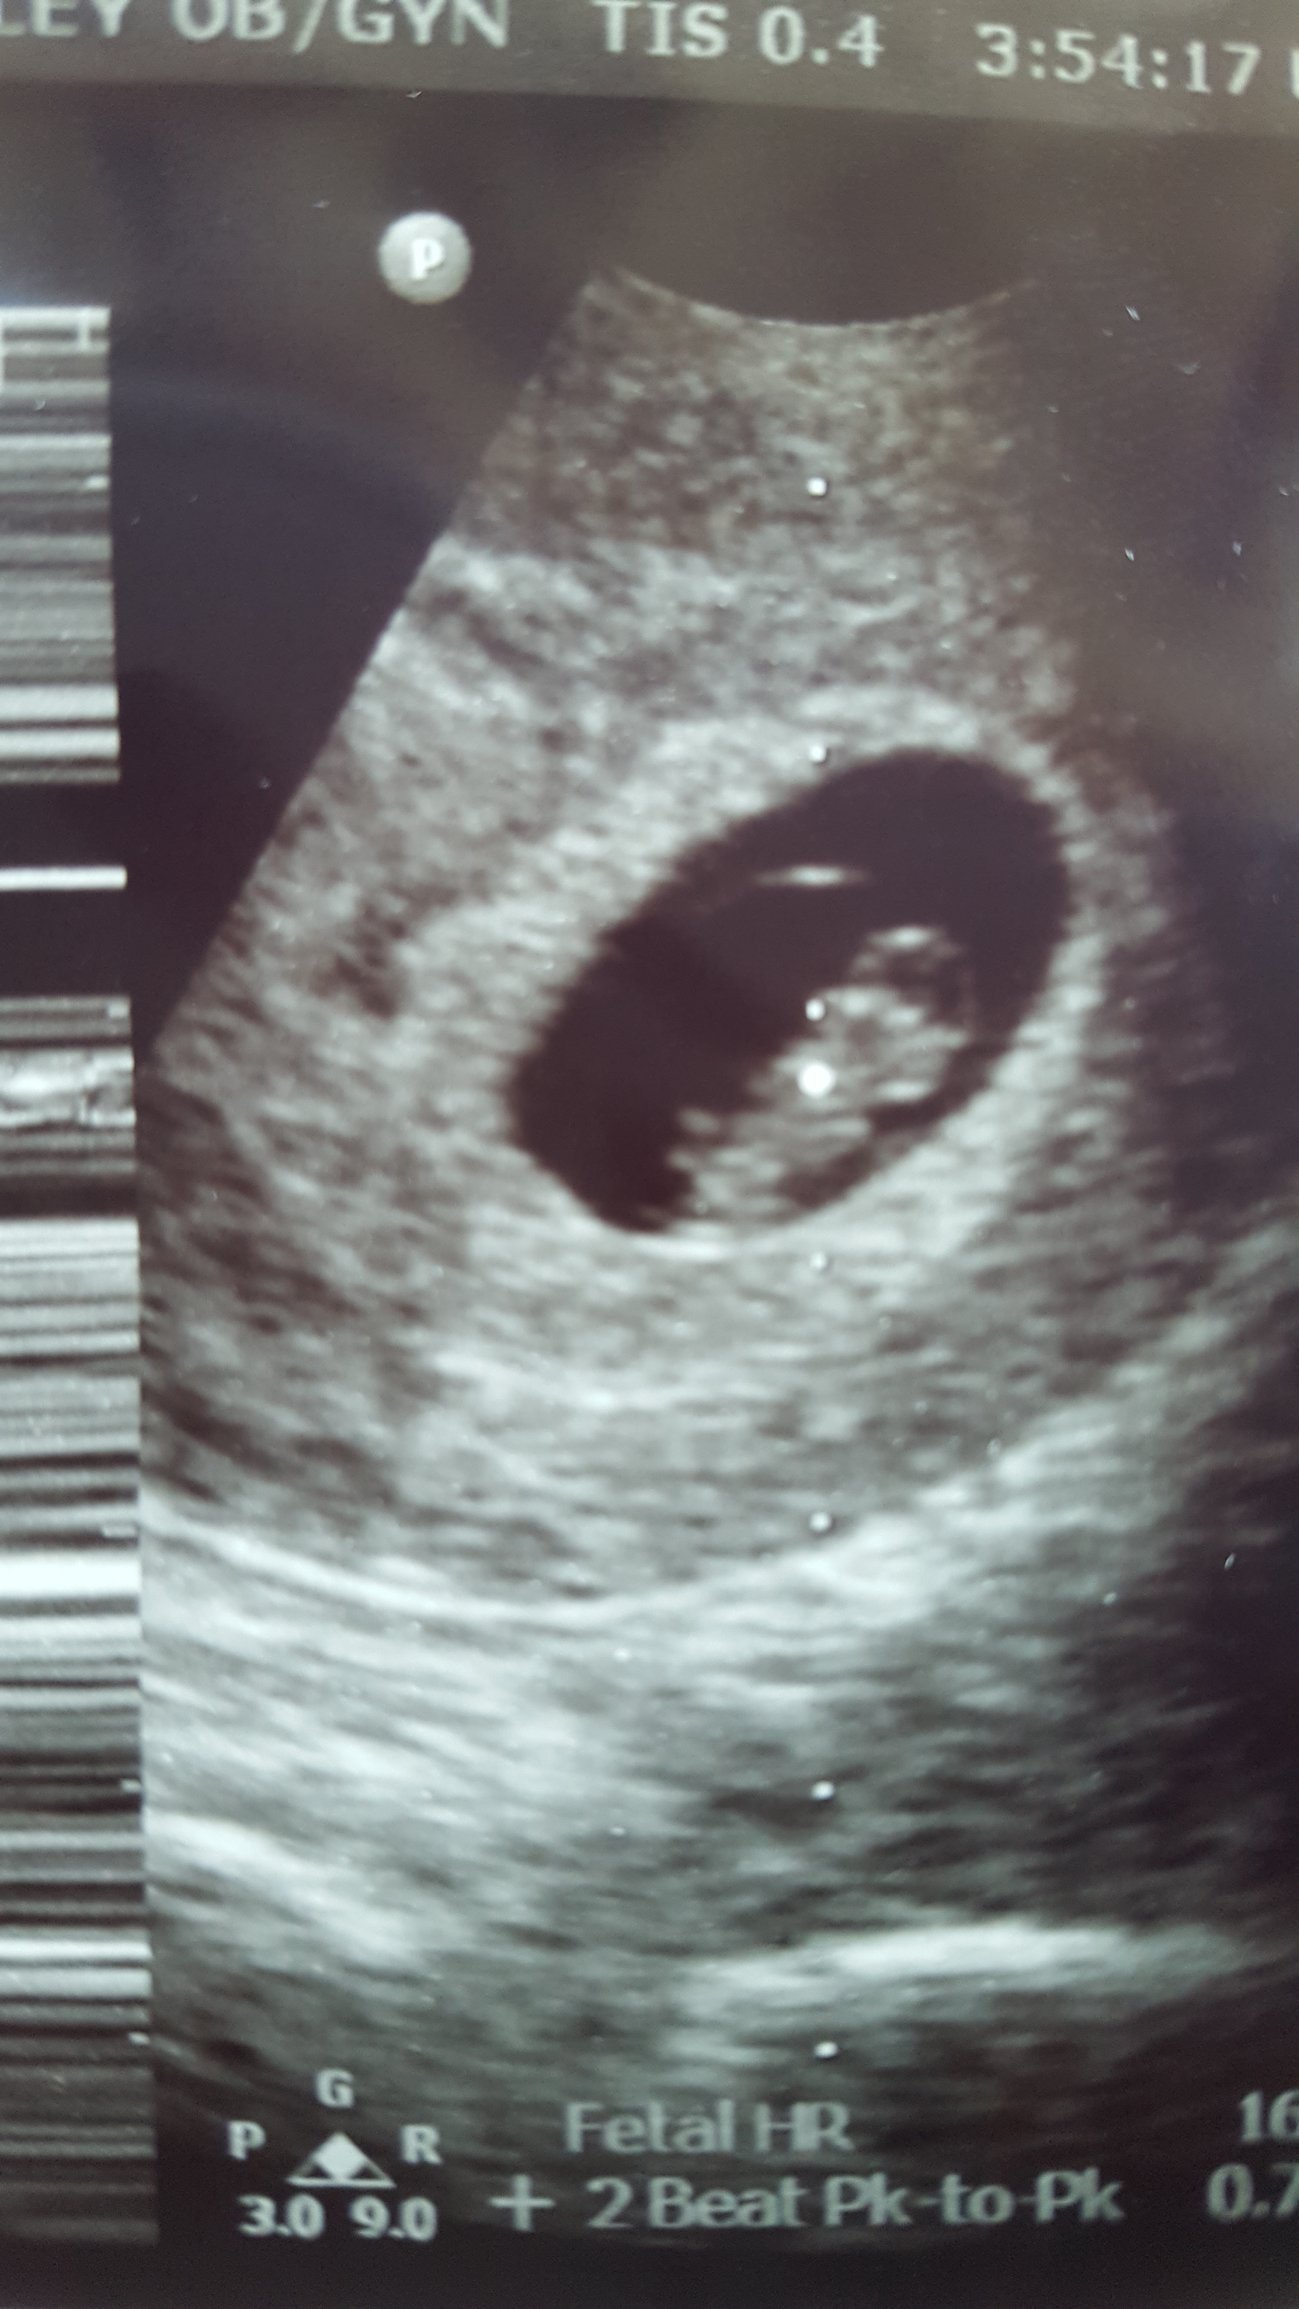

• Finally got to have our first ultrasound today!!! I'm at 9 weeks and 2 days, and the baby measured exactly that. Heart rate was 161 bpm, and we got to watch the heart beat on the monitor. The baby was bouncing and wiggling on the screen it was adorable. Did anyone else cry at their first ultrasound?!